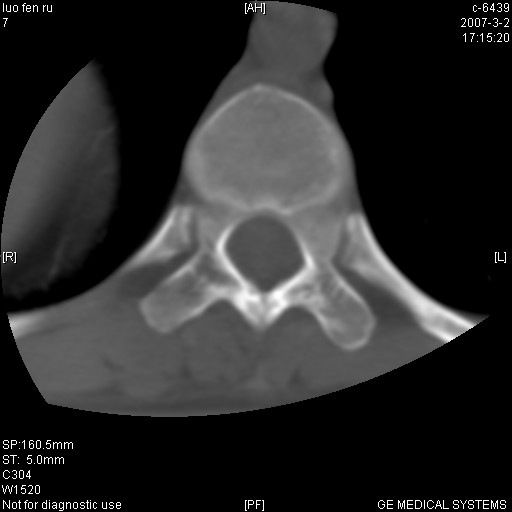

标题: CT6952:T11椎体病变请讨论

女,19岁.背部疼痛一月余.自诉幼时有个外伤史.

腰椎平片示,t11椎体呈楔形改变,椎间隙未见异常.

当是应是椎体(前半部较厉害)压缩性骨折,这就印证了这就是陈旧性骨折。

t11椎体前缘不规则形骨质破坏,周围有硬化边,软组织肿块不明显,首先考虑:骨嗜酸性肉芽肿 。期待随访结果。